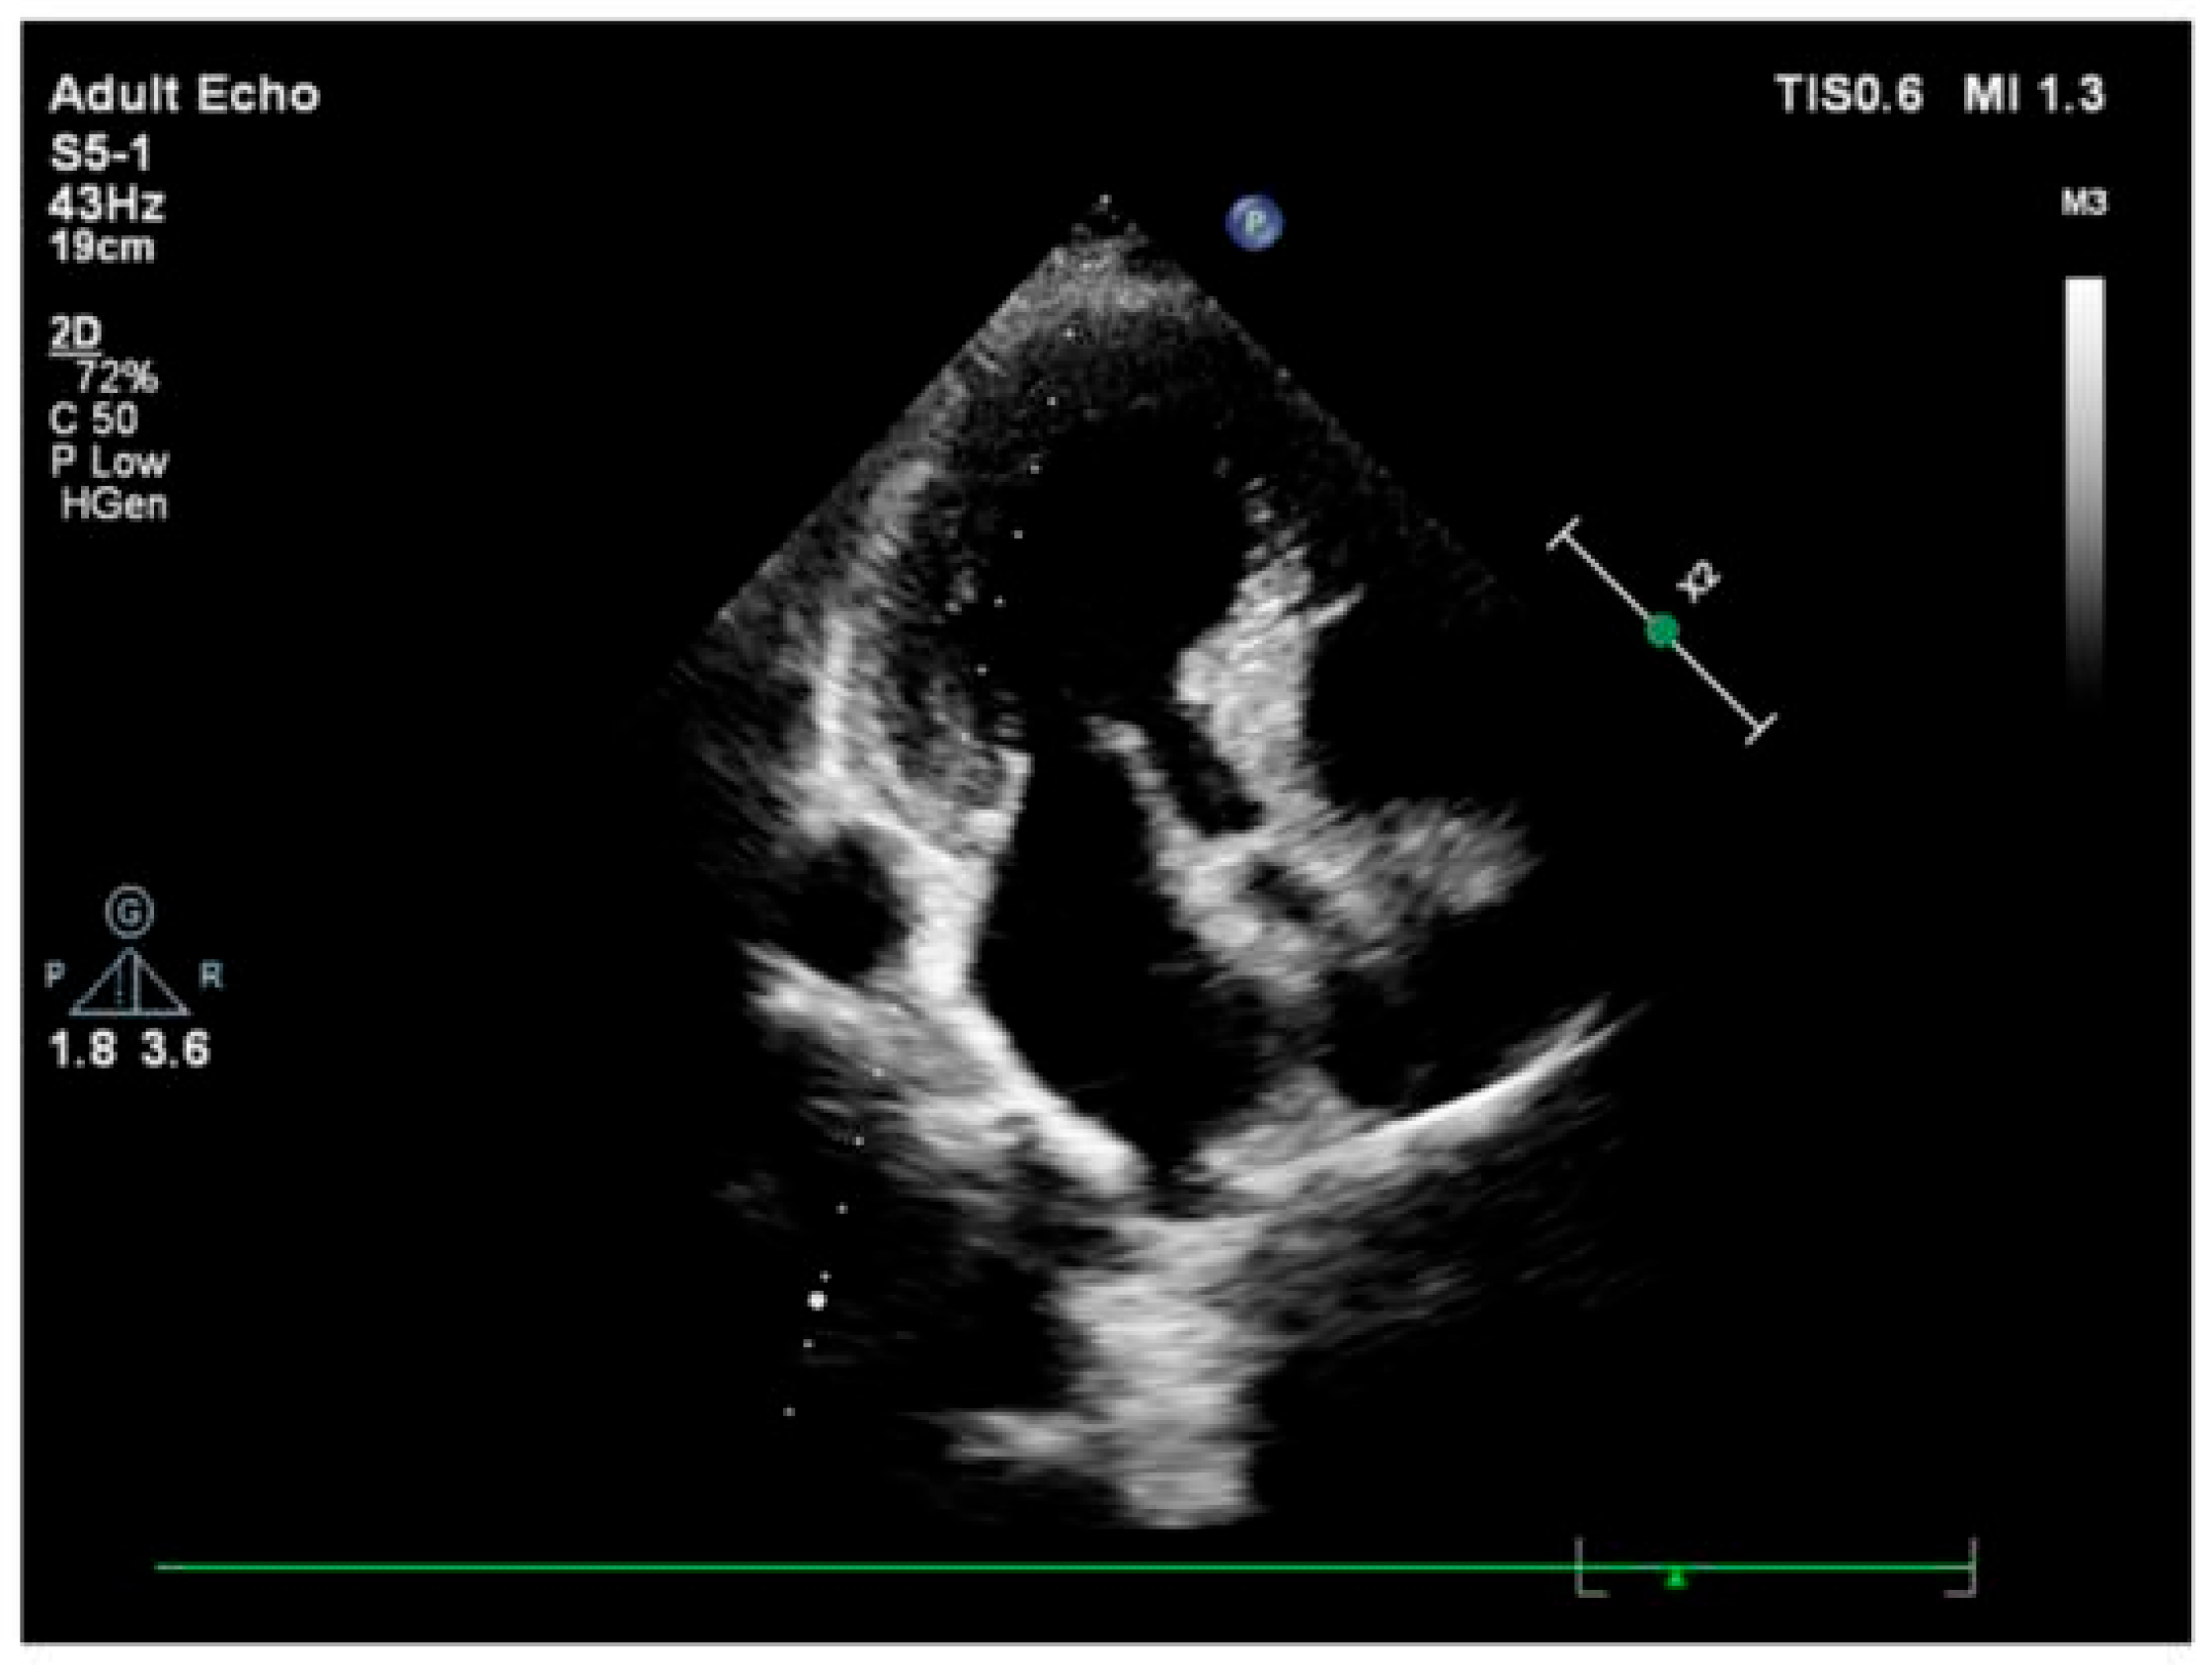

3.2. Imaging and Hemodynamic Observations

- Fefer, P.; Chelvanathan, A.; Dick, A.J.; Teitelbaum, E.J.; Strauss, B.H.; Cohen, E.A. Takotsubo Cardiomyopathy and Left Ventricular Outflow Tract Obstruction. J. Intervent. Cardiol. 2009, 22, 444–452. [Google Scholar] [CrossRef]

- Kawaji, T.; Shiomi, H.; Morimoto, T.; Tazaki, J.; Imai, M.; Saito, N.; Makiyama, T.; Shizuta, S.; Ono, K.; Kimura, T. Clinical Impact of Left Ventricular Outflow Tract Obstruction in Takotsubo Cardiomyopathy. Circ. J. Off. J. Jpn. Circ. Soc. 2015, 79, 839–846. [Google Scholar] [CrossRef]

- Çağatay, B.; Yalçin, F.; Kıraç, A.; Küçükler, N.; Abraham, M.R. The Science Behind Stress: From Theory to Clinic, Is Basal Septal Hypertrophy the Missing Link between Hypertension and Takotsubo Cardiomyopathy? Stresses 2024, 4, 330–341. [Google Scholar] [CrossRef]

- Abuarqoub, A.; Garis, R.; Shaaban, H.; Khaddash, I.; Shamoon, F. Takotsubo Cardiomyopathy with Basal Hypertrophy and Outflow Obstruction in a Patient with Bowel Ischemia. Int. J. Crit. Illn. Inj. Sci. 2018, 8, 44–47. [Google Scholar] [CrossRef]

- Yalçin, F.; Muderrisoǧlu, H. Tako-Tsubo Cardiomyopathy May Be Associated with Cardiac Geometric Features as Observed in Hypertensive Heart Disease. Int. J. Cardiol. 2009, 135, 251–252. [Google Scholar] [CrossRef]